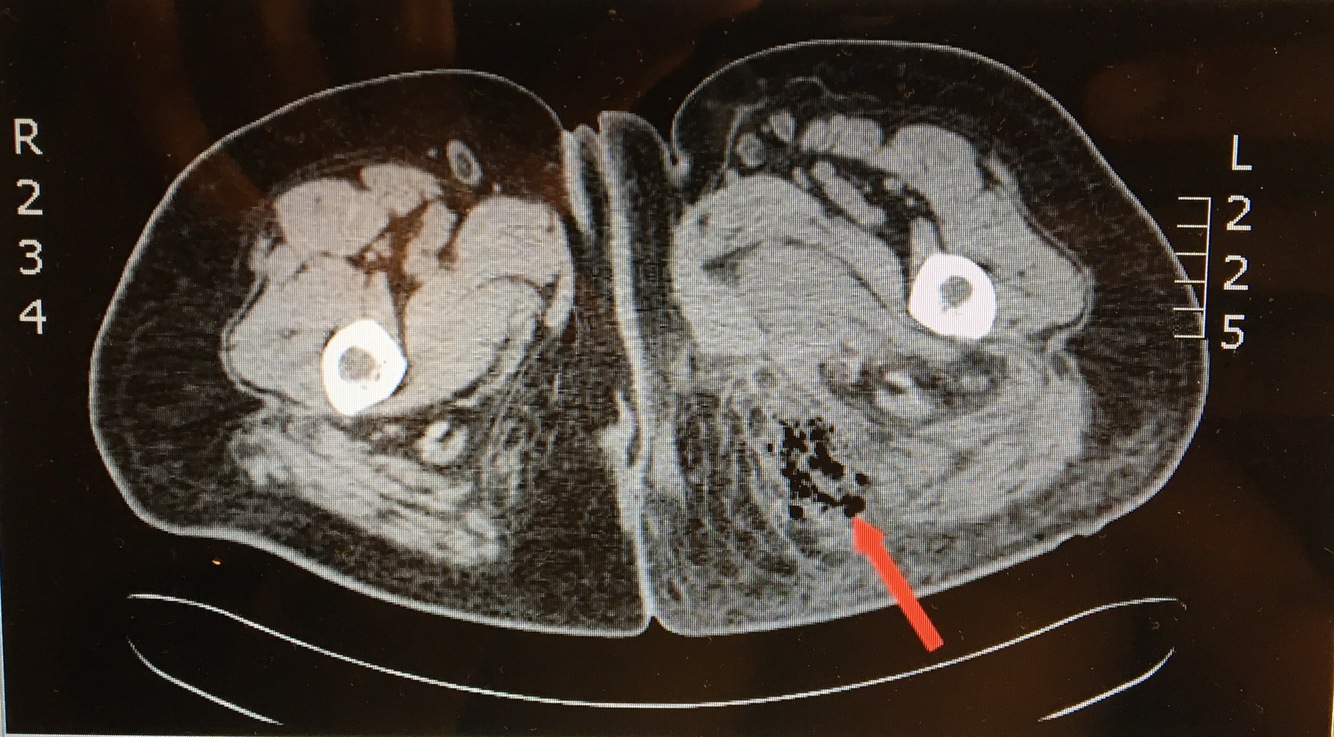

CT scan shows ______ which indicates _____. What causes this? Tx(2)?

[air in DEEP tissue]; Necrotizing Fasciitis;

[Group A Strep Pyogenes] (but typically polymicrobial) spreads rapidly thru SubQ & deep fascia after minor trauma –>

PAIN OUT OF PROPORTION WITH EXAM +

hypOtension +

[Erythema & Swelling]

Tx = Debridement + Broad Abx